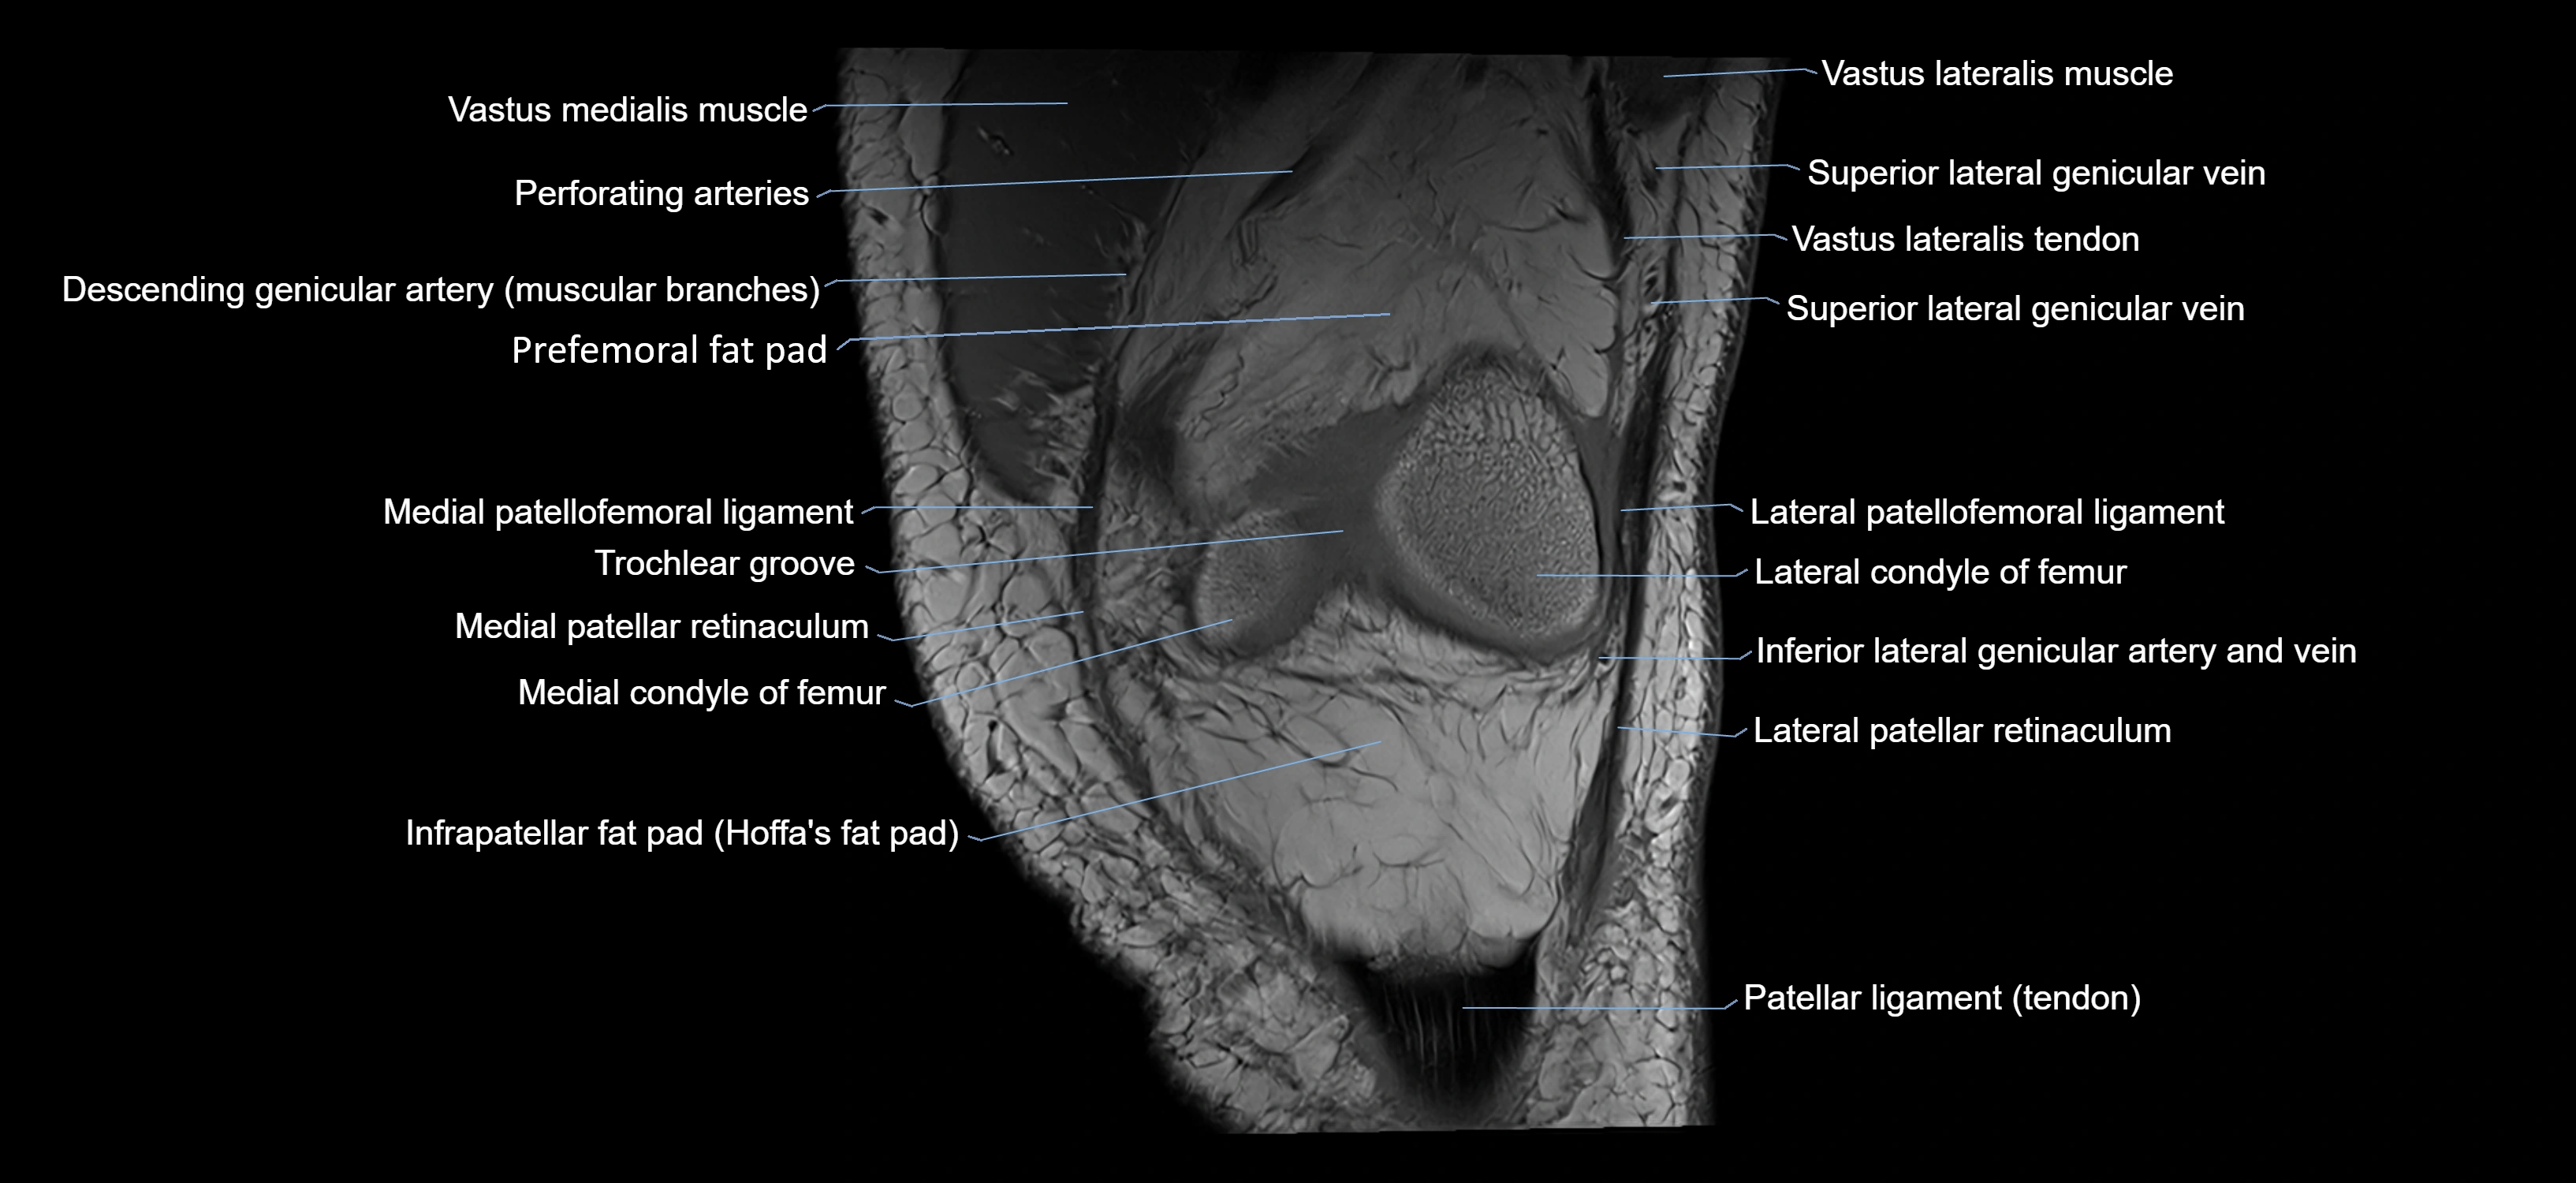

- Infrapatellar fat pad

- Lateral articular facet of patella

- Lateral condyle of femur

- Lateral patellar retinaculum

- Lateral patellofemoral ligament

- Medial condyle of femur

- Medial patellar retinaculum

- Medial patellofemoral ligament

- Patella

- Patellar articular cartilage

- Patellar tendon (patellar ligament)

- Prefemoral fat pad

- Superior lateral genicular vein

- Trochlear groove

- Vastus lateralis muscle

- Vastus medialis muscle